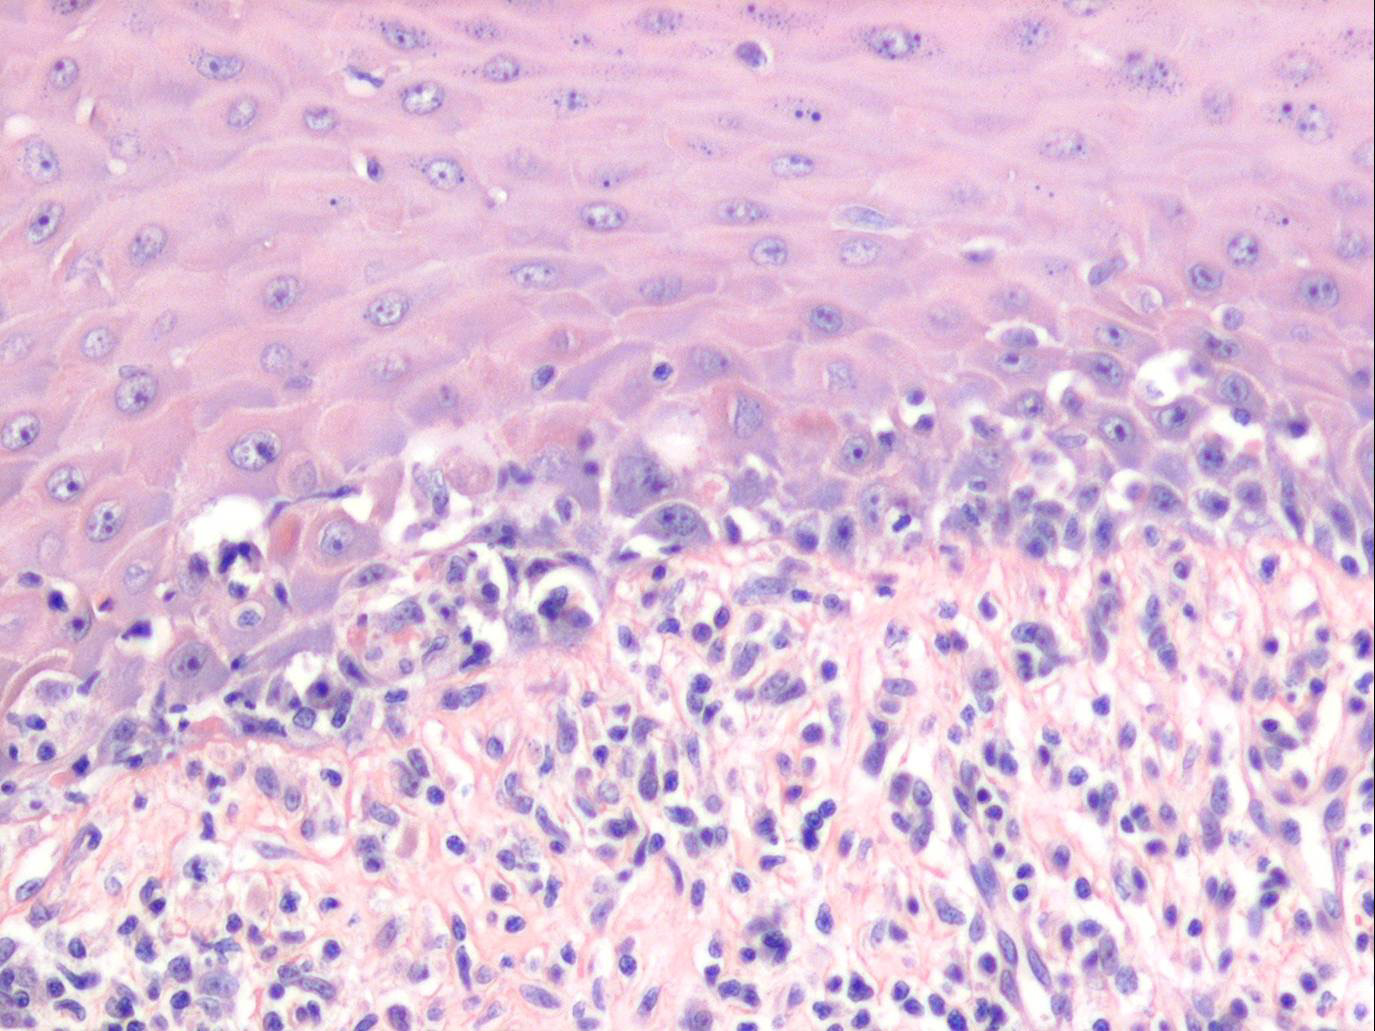

Oropharyngeal lichen planus = الحزاز المنبسط الفموي البلعومي